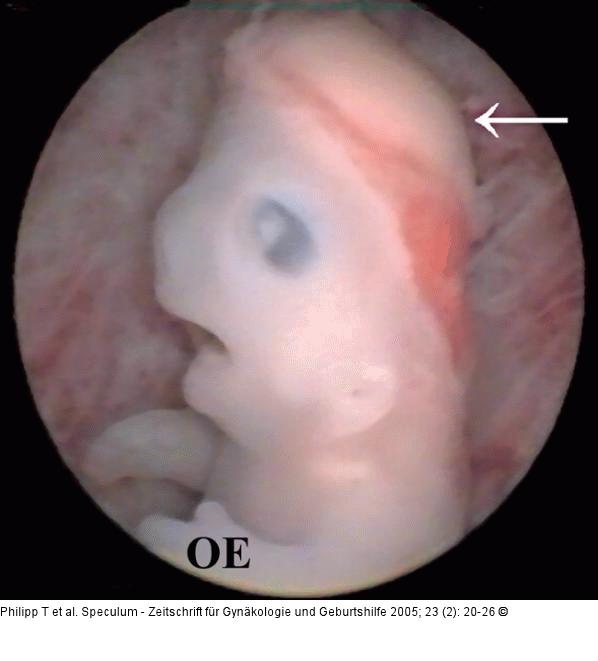

Abbildung 9: Embryo - Scheitel-Steißlage Seitenansicht eines Embryos von 22 mm SSL, mit normalem Karyotyp (46,XX). Der größte Teil des embryonalen Gehirns (Pfeil) liegt frei (Exenzephalie, Vorstadium einer Anenzephalie). (OE) markiert die linke obere Extremität. |

Abbildung 9: Embryo - Scheitel-Steißlage

Seitenansicht eines Embryos von 22 mm SSL, mit normalem Karyotyp (46,XX). Der größte Teil des embryonalen Gehirns (Pfeil) liegt frei (Exenzephalie, Vorstadium einer Anenzephalie). (OE) markiert die linke obere Extremität. |